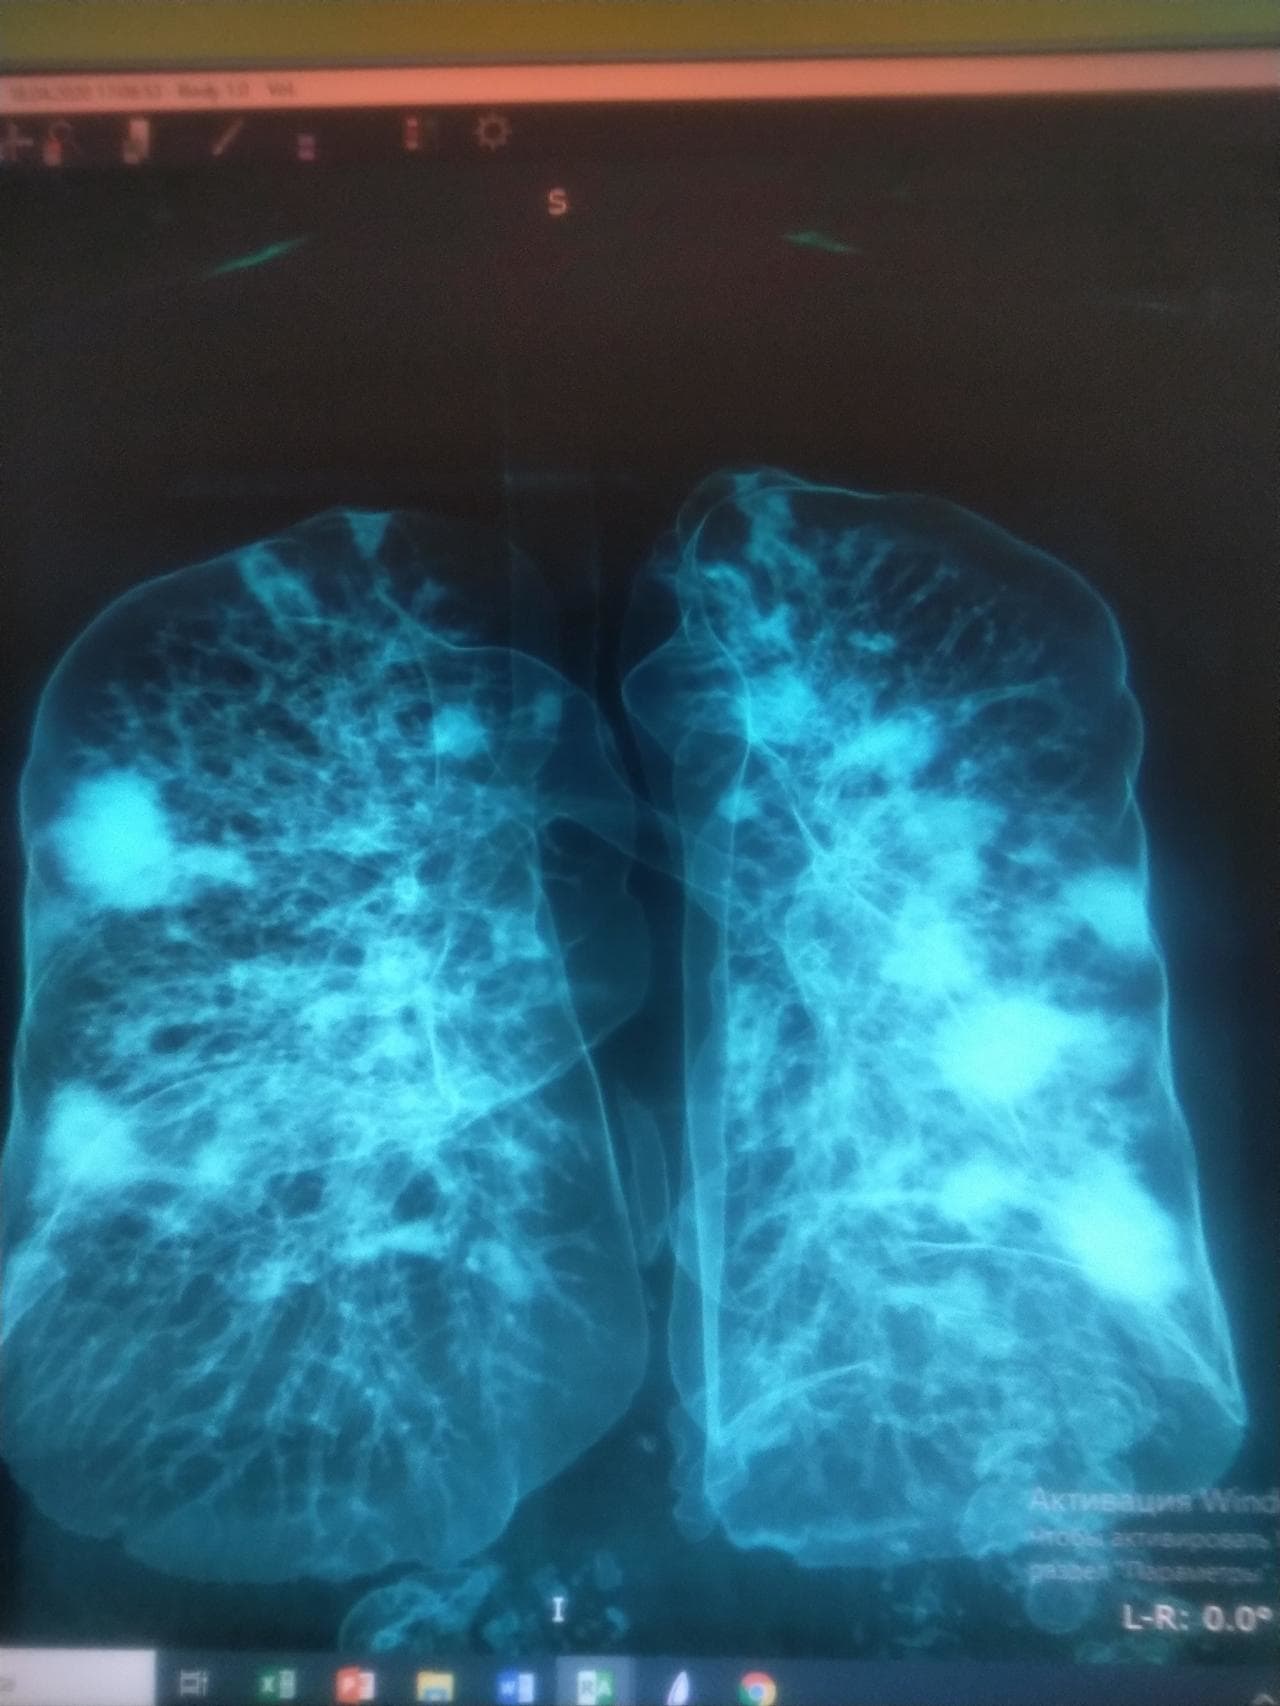

【衝撃】普通の人の「肺」とコロナ感染者の「肺」を比べた結果…(画像あり)

gif_animation ロシアサイトにて、普通の人の「肺」とコロナ感染者(重傷者)の「肺」のCT写真を比べた結果…が怖かった2枚の画像が話題に。どれだけの苦しみを。[2]images

※ コロナ感染者の「肺」(白く広がっている部分は全て炎症)